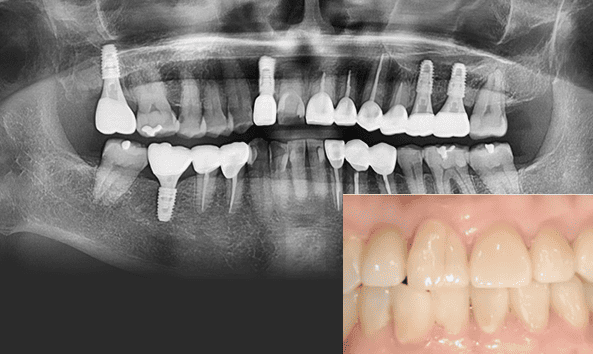

붓고 피나는 잇몸을 건강하게 잇몸치료로 회복하세요!

건강한 치아는 건강한 잇몸이 있기에 존재합니다. 성인의 절반 이상이 잇몸 질환을 모르고 방치하고 있습니다. 잇몸질환, 꾸준한 관리를 통해 개선해드리겠습니다.

잇몸 질환 치료에는 비수술적 치료와 수술적 치료 방법이 있습니다.

건강한 잇몸

치주낭 길이 3mm 이하

스케일링 치료

치은염

치주낭 길이 3~5mm 이하

치근활택술 치료

초기 치주염

치주낭 길이 5~7mm 이하

치주소파술 치료

중기 치주염

치주낭 길이 7mm 이상

치주 수술